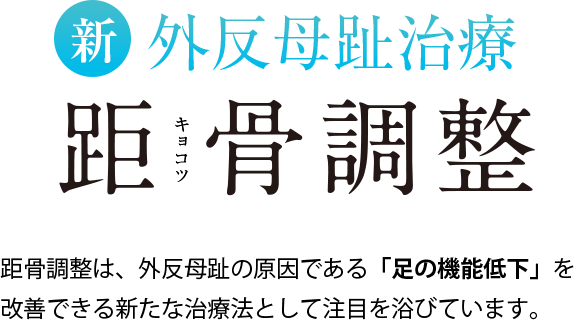

志水式整体では、人間の土台である「骨盤」と「足元(距骨)」をセットに考え、整えることにより、重力に負けない対応力を取り戻す「究極の土台調整」を行っております。

慢性的な膝や腰の痛み、頭痛、肩こり、外反母趾、骨盤の歪み、婦人科系疾患、慢性疲労、不眠、カラダのたるみ、便秘と多様な悩みに苦しむ方をこれまで施術してきましたが、どの方も共通していたのは「距骨」が歪んでいたことでした。 日常的な様々な痛みや症状の原因は、この土台である距骨にあるのです。

距骨を整える事により痛みの無い健康なカラダを取り戻して行きます。